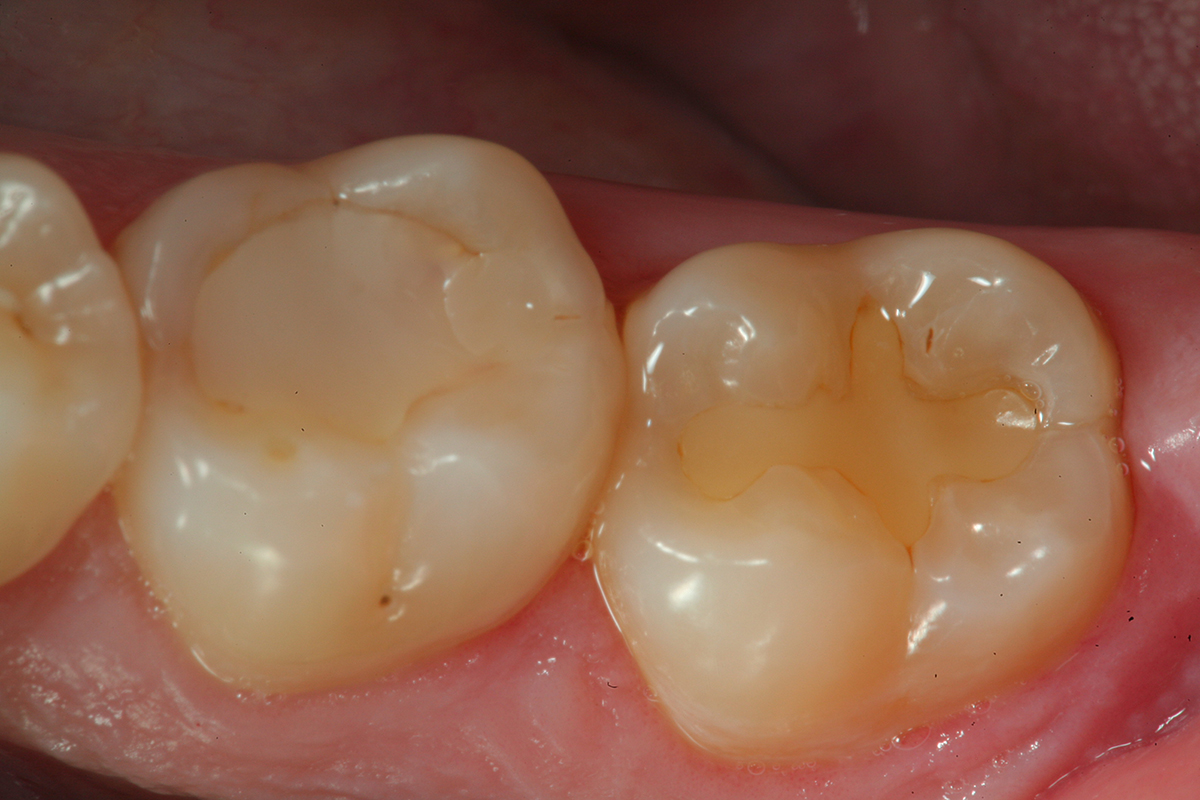

Fig 1. A preoperative occlusal view of tooth No. 13 that has a “stain” in the occlusal groove that does not “stick” with an explorer.

Figure 1